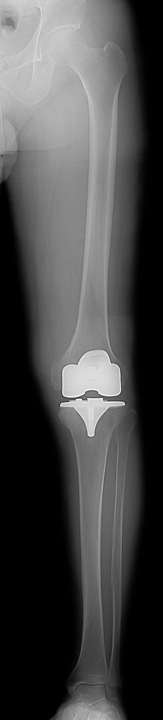

![]() 術後レントゲン |

人工膝関節置換術とは、傷んで変形した関節を人工の関節に置き換える手術です。人工関節の表面は滑らかで神経もないため、この手術を受けることによって、関節は滑らかに動くようになり、痛みもほとんど感じなくなります。また、O脚やX脚に変形した膝が、手術によって真っすぐな膝になります。痛みなく歩けるようになると、日常生活を送りやすくなり、生活の質(QOL)を改善することができます。

手術では、まず変形して傷んだ大腿骨と脛骨の表面の骨を切除します。大腿骨側と脛骨側の骨にそれぞれ金属製の人工関節(大腿骨・脛骨コンポーネント)を固定します。脛骨コンポーネントの上面に超高分子量ポリエチレン製の人工の軟骨(インサート)を設置します。人工膝関節は大腿骨コンポーネントとインサートの間で滑らかに動く構造になっています。